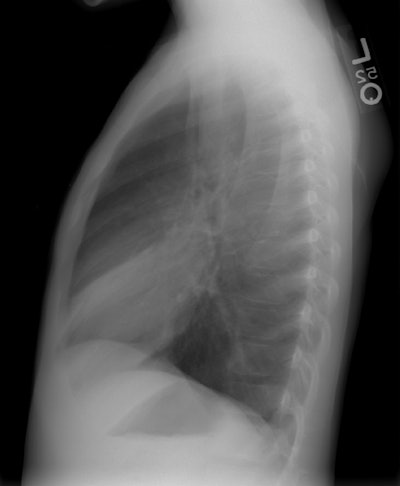

The patient below was an 8 year old boy who had repeated episodes

of sinusitis and recurrent upper respiratory infections. The chest

radiograph demonstrates both cardiac and abdominal situs inversus.

There is a left lingular infiltrate (best seen on the lateral

view). A sinus CT on this patients demonstrates evidence of pansinusitis